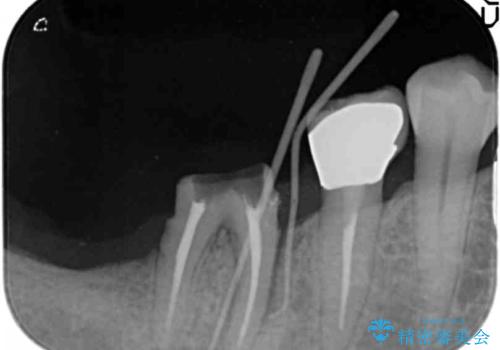

- 「奥歯で噛むと痛い、いつも膿のにおいがして不快、改善してほしい。」と治療を希望され来院されました。

精査した結果、奥歯の根は破折しており抜歯を避けられない状況でした。

咬合力が強く、その他の歯の破折も防ぐために奥歯の咬合機能をインプラントを用いて回復する治療計画を立てます。